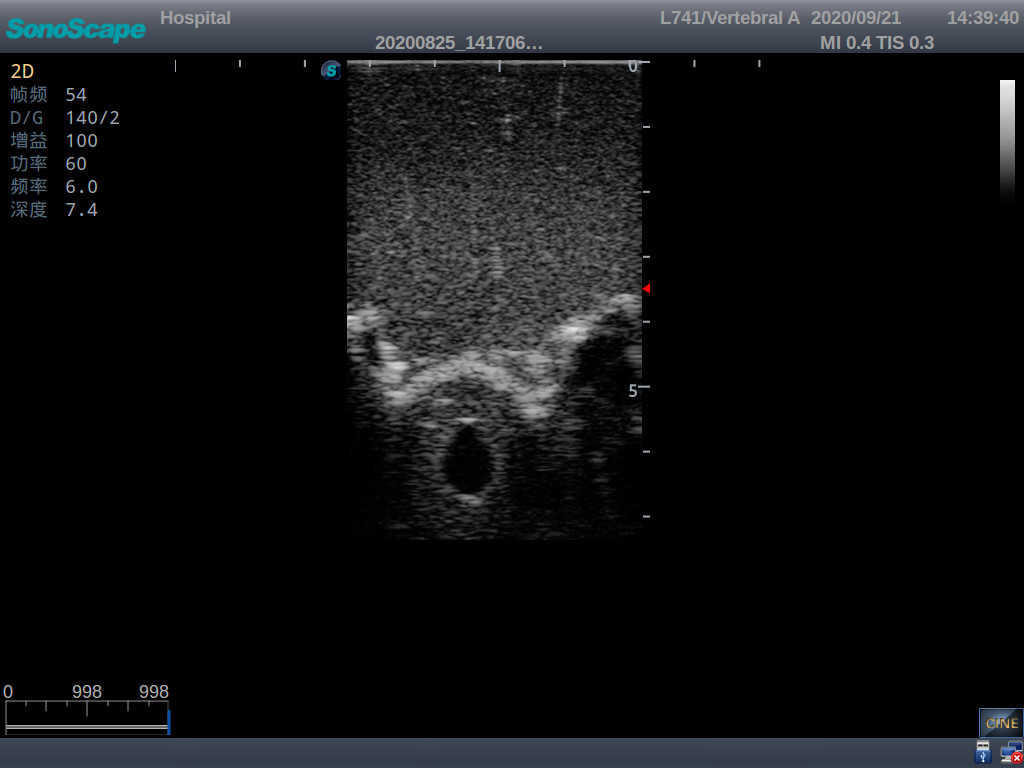

Adult Lumbar Puncture Ultrasound Training Model

Model TYE1549.2

This model is an ideal choice for ultrasound-guided adult lumbar puncture training with true-to-life skin feel and touch, accurate anatomical structures as well as real clinical ultrasound images. Realistic resistance to needle tips and correct landmarks provide excellent hands-on experience.

Accurate anatomical structure of L1-L5 and the vertebral canal

2)  Real clinical ultrasound images

3)  Compatible with various real ultrasound machines